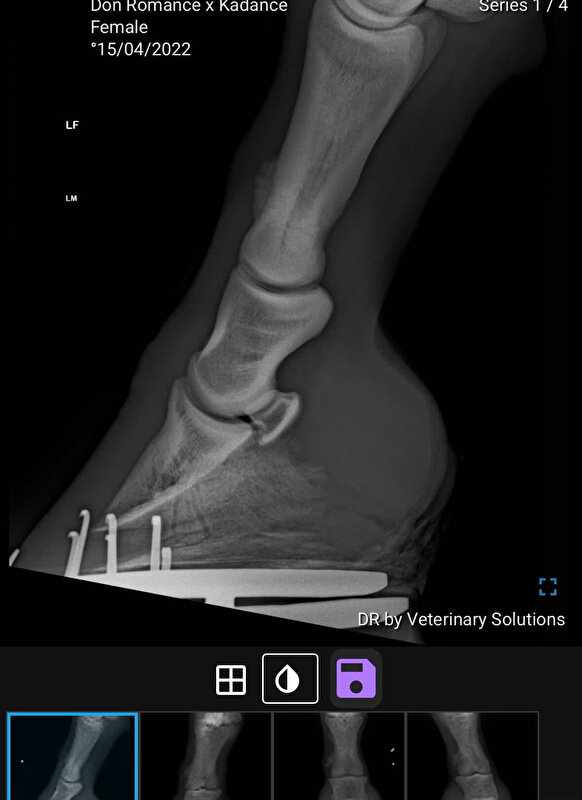

Op 06-03-2026 zijn we voor controle geweest. Na het klinische beeld mochten we zelfs weer opbouwen. Tot schrik van iedereen bleek bij de controle foto’s dat er toch een scheur/fissuur in haar kootbeen zat, maar deze zat op een andere plek dan haar eerdere bot trauma. Deze fissuur was niet zichtbaar bij de eerdere foto’s.

Nu staan we voor de volgende opties:

- Jaar lang rust geven en daarna weer eens kijken met een röntgen foto hoe het hersteld.

- CT Scan om te kijken of het operabel is en de fissuur beter in kaart te brengen

-Eventueel opereren / stabiliseren met schroeven, dit moet nog uit de CT blijken

-Extra optie vanuit een andere kliniek was nog gips verband of een Robert Jones spalk

Eerste foto is op 23-01 en tweede op 06-03